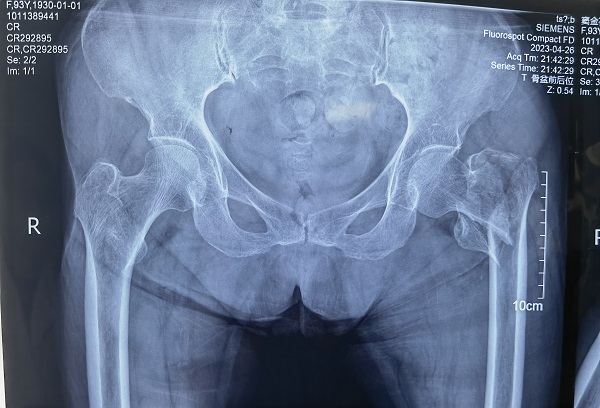

人工关节置换术在关节外科领域属于高难度、高风险手术,尤其对于高龄患者而言更是如此。近日,二一五医院骨科医院脊柱外科成功为一名93岁高龄患者完成左侧人工半髋关节置换术。 半个多月前,93岁的豆奶奶在家中上厕所...